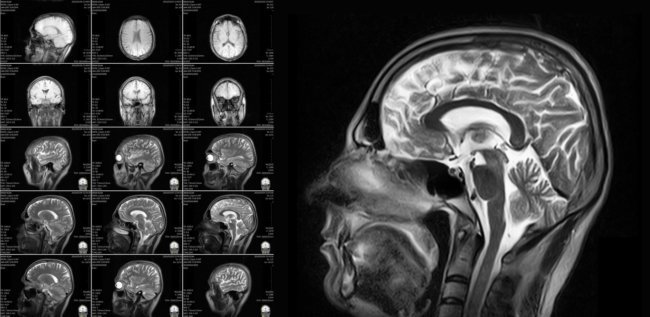

С помощью сканирования мозга можно диагностировать депрессию и болезнь Альцгеймера. Но можно ли объяснить поведение человека с помощью визуализации головного мозга? ?

, , . ( 23 ).